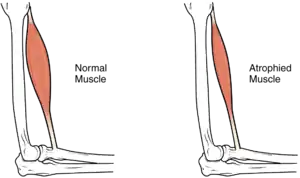

In the long term, the loss of muscle function can have additional effects from disuse, including atrophy of the muscle. Immobility can lead to pressure sores, particularly in bony areas, requiring precautions such as extra cushioning and turning in bed every two hours (in the acute setting) to relieve pressure.[51] In the long term, people in wheelchairs must shift periodically to relieve pressure.[52] Another complication is pain, including nociceptive pain (indication of potential or actual tissue damage) and neuropathic pain, when nerves affected by damage convey erroneous pain signals in the absence of noxious stimuli.[53] Spasticity, the uncontrollable tensing of muscles below the level of injury, occurs in 65–78% of chronic SCI.[54] It results from lack of input from the brain that quells muscle responses to stretch reflexes.[55] It can be treated with drugs and physical therapy.[55] Spasticity increases the risk of contractures (shortening of muscles, tendons, or ligaments that result from lack of use of a limb); this problem can be prevented by moving the limb through its full range of motion multiple times a day.[56] Another problem lack of mobility can cause is loss of bone density and changes in bone structure.[57][58] Loss of bone density (bone demineralization), thought to be due to lack of input from weakened or paralysed muscles, can increase the risk of fractures.[59] Conversely, a poorly understood phenomenon is the overgrowth of bone tissue in soft tissue areas, called heterotopic ossification.[60] It occurs below the level of injury, possibly as a result of inflammation, and happens to a clinically significant extent in 27% of people.[60]